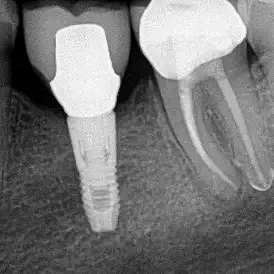

Fall 1: Revisionsbehandlung

Ausgangssituation

Kontrolle nach Wurzelfüllung